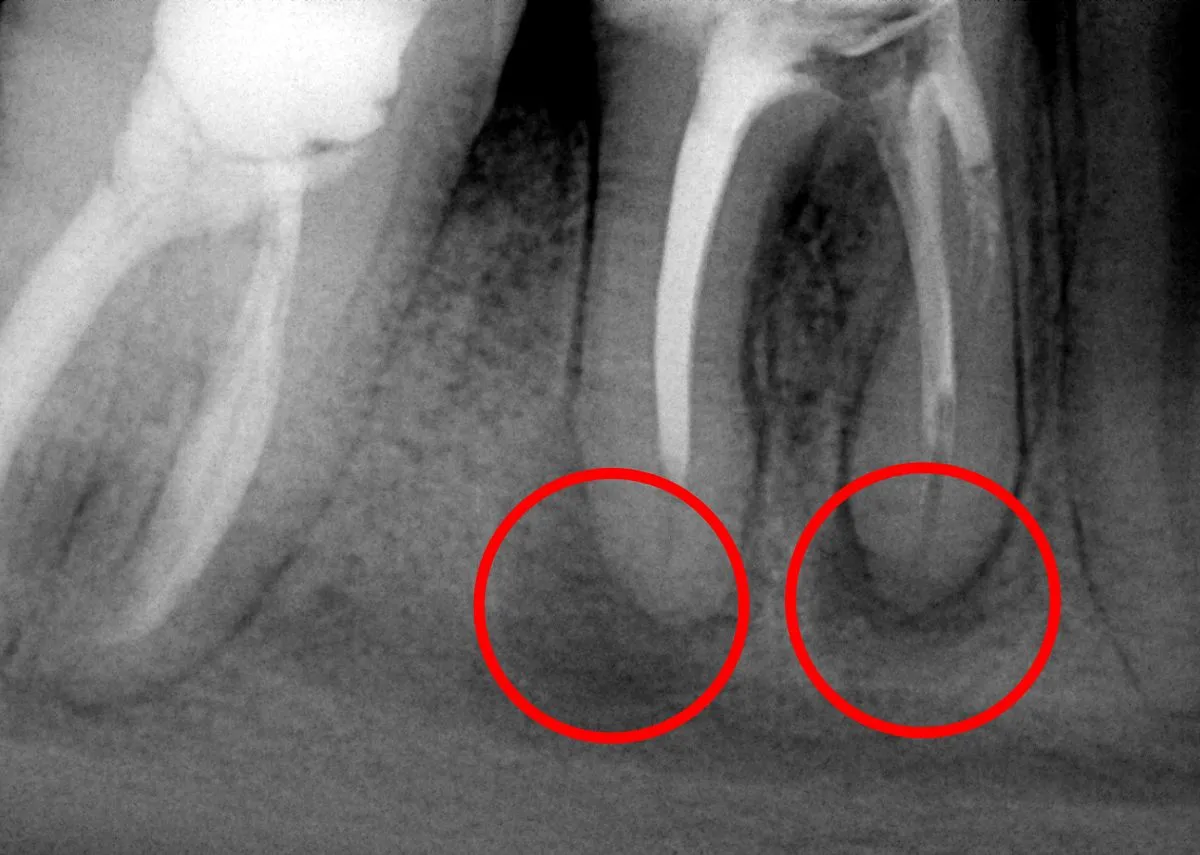

Choć potocznie mówimy o "torbieli na dziąśle", w stomatologii wyróżniamy kilka typów tych zmian, różniących się pochodzeniem i charakterystyką. Najczęściej spotykana jest torbiel korzeniowa. Jak sama nazwa wskazuje, powstaje ona wokół wierzchołka korzenia zęba i jest bezpośrednim następstwem przewlekłego stanu zapalnego, często wynikającego z nieleczonej próchnicy lub martwicy miazgi. To właśnie ten typ torbieli najczęściej wykrywamy na zdjęciach rentgenowskich.

Kluczowym elementem w diagnostyce torbieli jest zdjęcie rentgenowskie. Torbiele często są wykrywane przypadkowo podczas rutynowych zdjęć pantomograficznych (panoramicznych) lub punktowych. Na zdjęciu RTG torbiel widoczna jest jako owalne, ciemniejsze przejaśnienie w kości, co świadczy o ubytku tkanki kostnej. To właśnie dzięki RTG możemy ocenić jej rozmiar, lokalizację i związek z otaczającymi strukturami, takimi jak korzenie zębów czy nerwy.